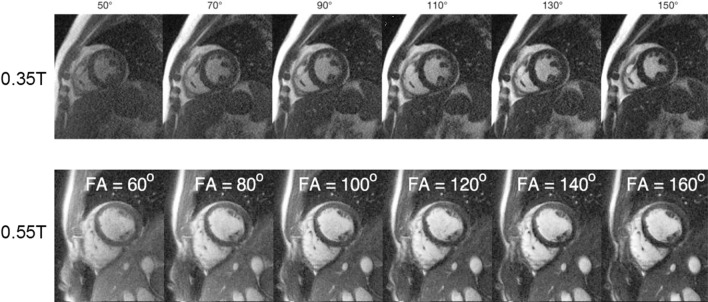

Researchers have also studied protocol improvements to compensate for the reduced SNR due to polarization at 0.35 T [33] and 0.55 T [40], which suggest the use of higher flip angles and longer readouts. Figure 2 shows an example of bSSFP cardiac cine images acquired with different flip angles at 0.35 T and 0.55 T, demonstrating a high flip angle (usually ≥ 90°) yields the optimal blood-myocardium contract. The use of a high flip angle at 1.5 T or 3 T is usually problematic due to the SAR constraints. Low-field systems also support contrast-optimal flip angle for simultaneous multi-slice (SMS) bSSFP, as reported by Tian et al. [40]. Restivo et al. [41] demonstrated that with an SNR efficient sampling trajectories such as spiral in–out readout, there is a 79% increase in the SNR when compared with Cartesian readout, and the SNR reduction when compared with 1.5 T Cartesian is 48% in the blood and 31% in the myocardium. These SNR-efficient techniques such as SMS and long readout may be problematic at higher field strength due to increased SAR and off-resonance artifacts. On the 0.75 T system, Peereboom et al. [42] measured T1, T2, and T2* in the myocardium, and demonstrated that by leveraging these physical prosperities in the pulse sequence design accurate myocardial spectroscopy measurement can be achieved at 0.75 T.

Fig. 2.

Blood-myocardium contrast changes with a flip angle. The apparent contrast between the blood and the myocardium increases as the bSSFP flip angle increases and peaks at flip angle = 130° at 035 T and at flip angle = 160° at 0.55 T. Note that the blood signal is not in a steady state due to the constant inflow in the ventricular, which increases the signal intensity. This resulted in a higher contrast-optimal flip angle in the experiment than in the steady-state Bloch simulation. A high flip angle can be applied within a reasonable TR without exceeding the SAR limitation on low-field systems. At 1.5 T or 3 T, applying a high flip angle may prolong the TR, which can introduce more banding artifacts for bSSFP cine. 0.35 T images are reproduced from Rashid et al. [33] and the 0.55 T images are reproduced from Tian et al. [40]